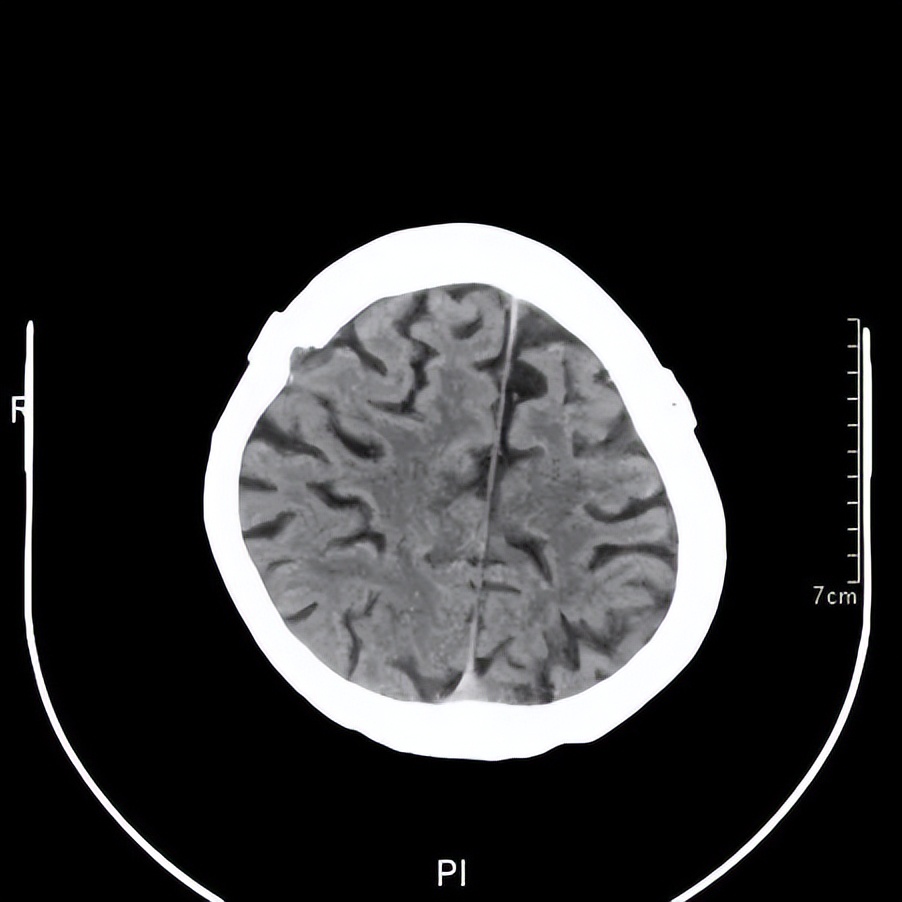

王阿婆手术后引流置管状态的头颅CT